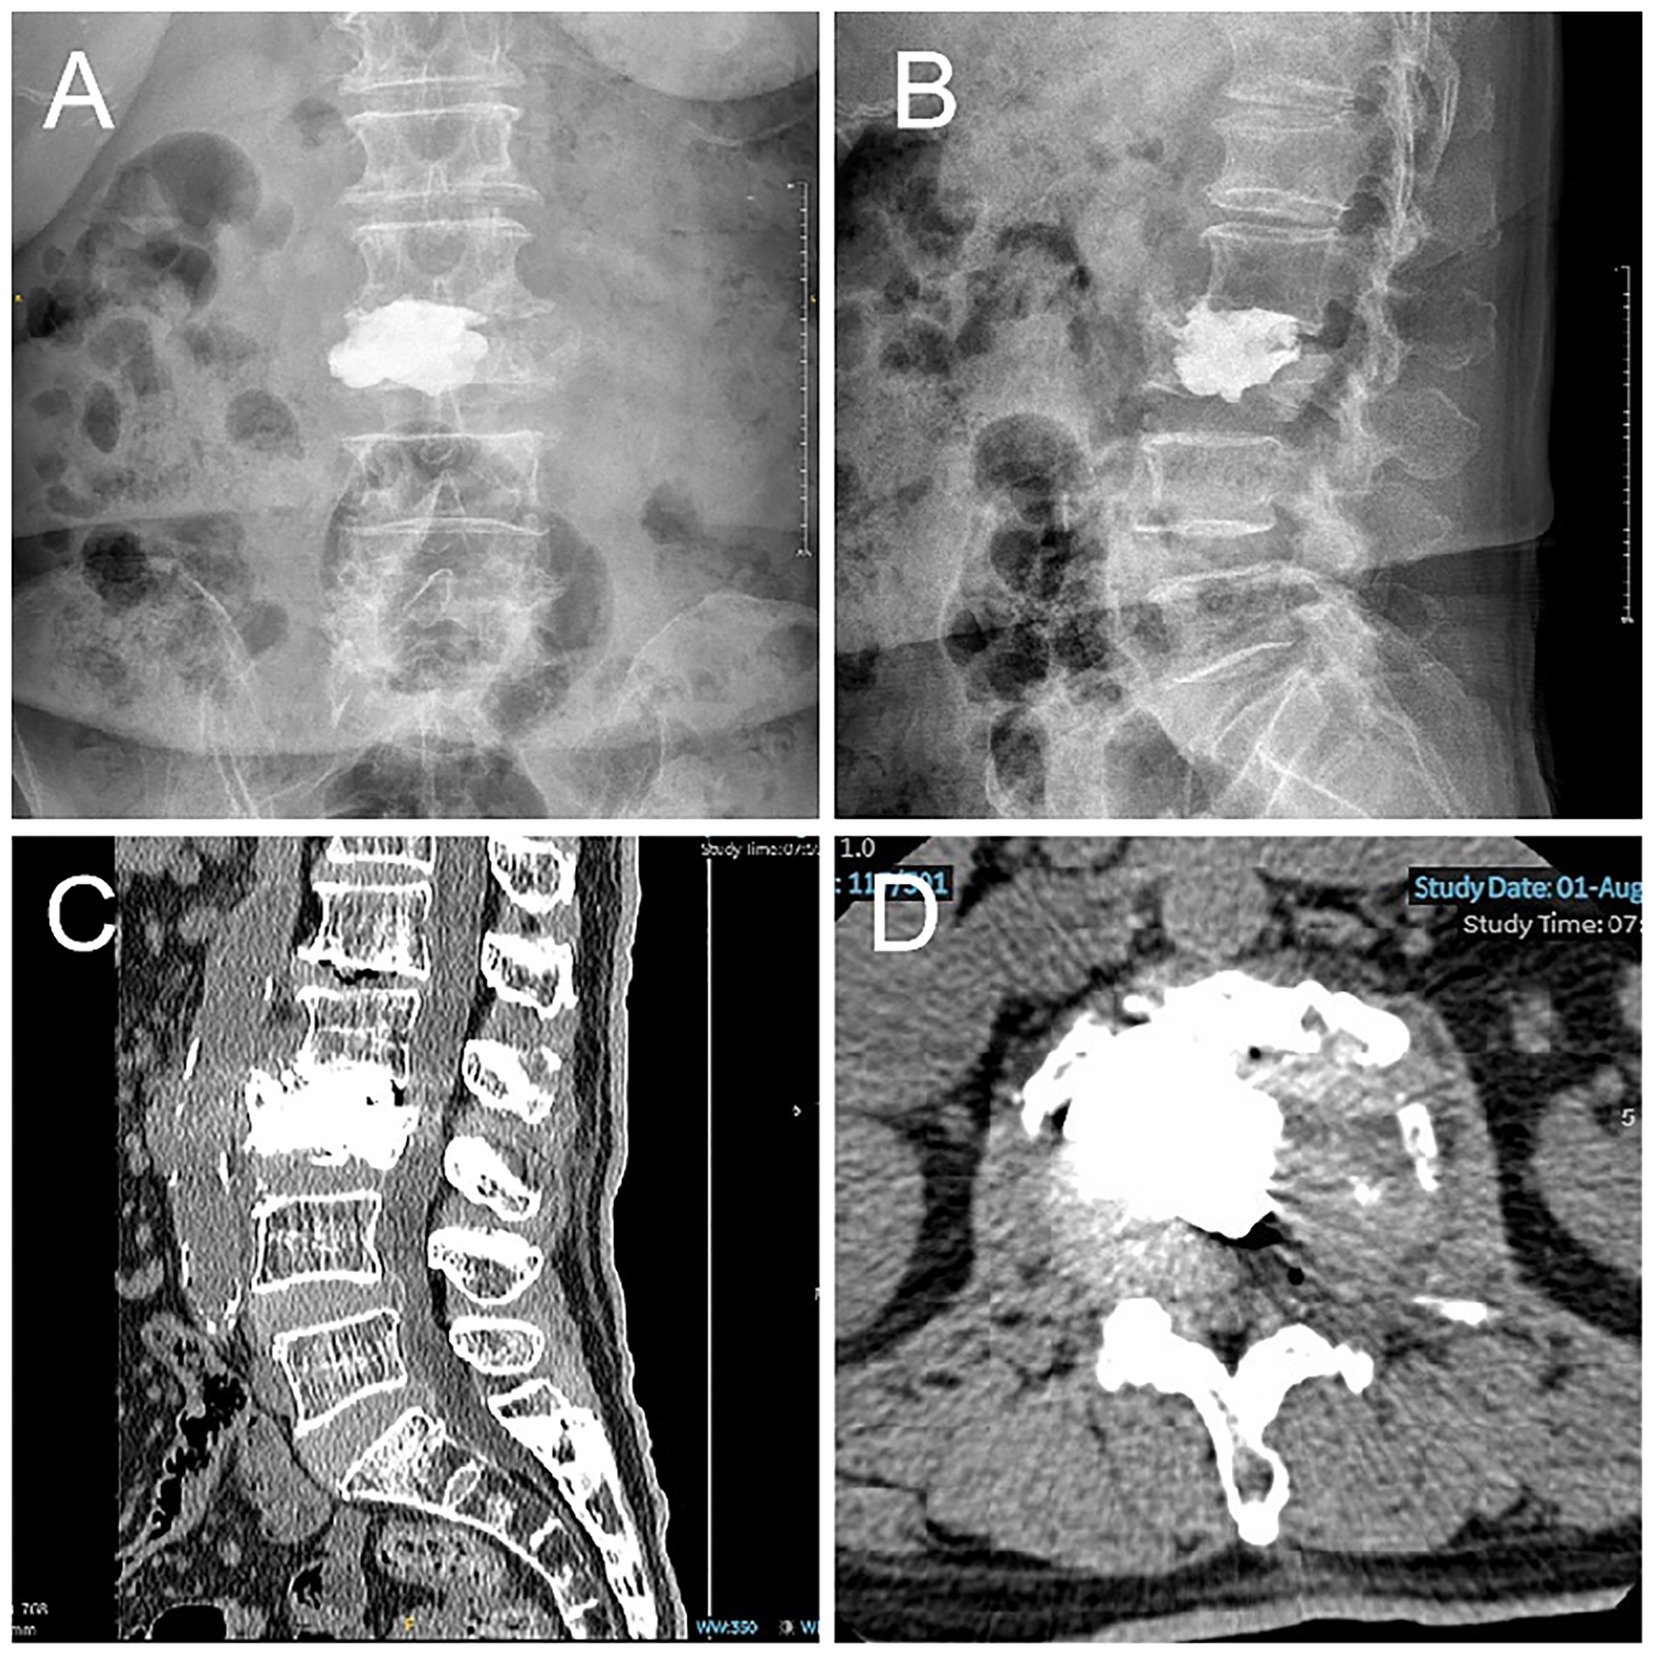

Figure 3

Postoperative lumbar radiographs and CT. Cement is satisfactorily placed within the L3 vertebral body and the L2/3 intervertebral disk. Postoperative imaging demonstrates resolution of the focal kyphotic deformity, restoration of normal spinal alignment, and complete decompression of the L2/3 neural foramen and lateral recess.

However, it is imperative to acknowledge the limitations of this approach. Firstly, it should be noted that this report describes a single case, and thus the generalizability of the technique remains uncertain. Although short-term clinical and radiographic outcomes were favorable, long-term follow-up is necessary to assess the durability of vertebral height restoration and risk of adjacent segment degeneration or recurrent collapse. Furthermore, the postoperative follow-up CT revealed the presence of partial absence of bone cement in the intervertebral disk due to inadequate local filling (29) (Figure 4). This may result in complications or prognostic risks that necessitate further follow-up and sample studies.

Figure 4

Postoperative lumbar CT scan indicates partial absence of intervertebral disk bone cement. (A–B) Lumbar Spine Digital X-Ray Radiography. (C–D) Lumbar spine CT.